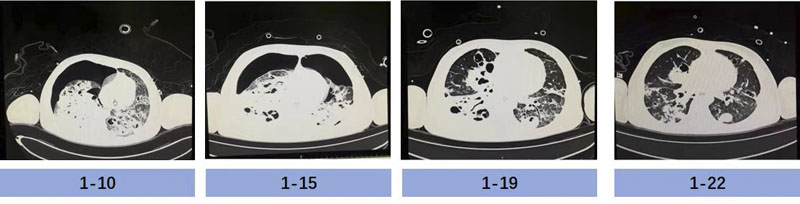

成功撤离ECMO,只是“生命闯关”的第一步,如何控制感染、恢复肺功能、脱离呼吸机支持、避免院内感染及获得性肌无力,是医护人员面对的又一个难题。根据基因测序及培养结果回报,患儿血液及肺泡灌洗液标本中均检出大量金黄色葡萄球菌(基因序列数高达一百多万条)及流感嗜血杆菌(基因序列数高达二十多万条),两者叠加,破坏力巨大;患儿肺部影像学提示:双肺大面积实变、渗出及空洞,极易引发自发性气胸。

胡振杰主任临床经验丰富,在病原学结果回报之前就判断患儿金黄色葡萄球菌感染可能性大,结合迅速发展的多脏器功能衰竭症状,第一时间应用了广谱抗生素(美罗培南联合利奈唑胺)抗感染治疗。随着药敏结果回报,金黄色葡萄球菌为敏感菌株,指南推荐甲氧西林敏感的金葡菌(MSSA)肺炎首选抗葡萄球菌青霉素类与一代头孢,而甲氧西林耐药的金葡菌(MRSA)肺炎首选万古霉素、利奈唑胺。考虑到患儿并不是单纯的MSSA肺炎,合并血流感染及多脏器功能衰竭,并且对头孢类药物过敏,抗生素选择应精准且符合实际,斟酌再三,胡振杰主任毅然选择了单纯应用哌拉西林他唑巴坦抗感染治疗,一定程度上避免了广谱抗生素导致的耐药菌发生。为更好地改善患儿肺部通气不均一性,医护人员协助患者行俯卧位通气治疗,密切监测肺部体征和影像学评估,第一时间发现气胸并紧急请胸外科医师为患儿行胸腔闭式引流术,反复调整引流管位置,给予负压吸引,进一步促进肺泡扩张。